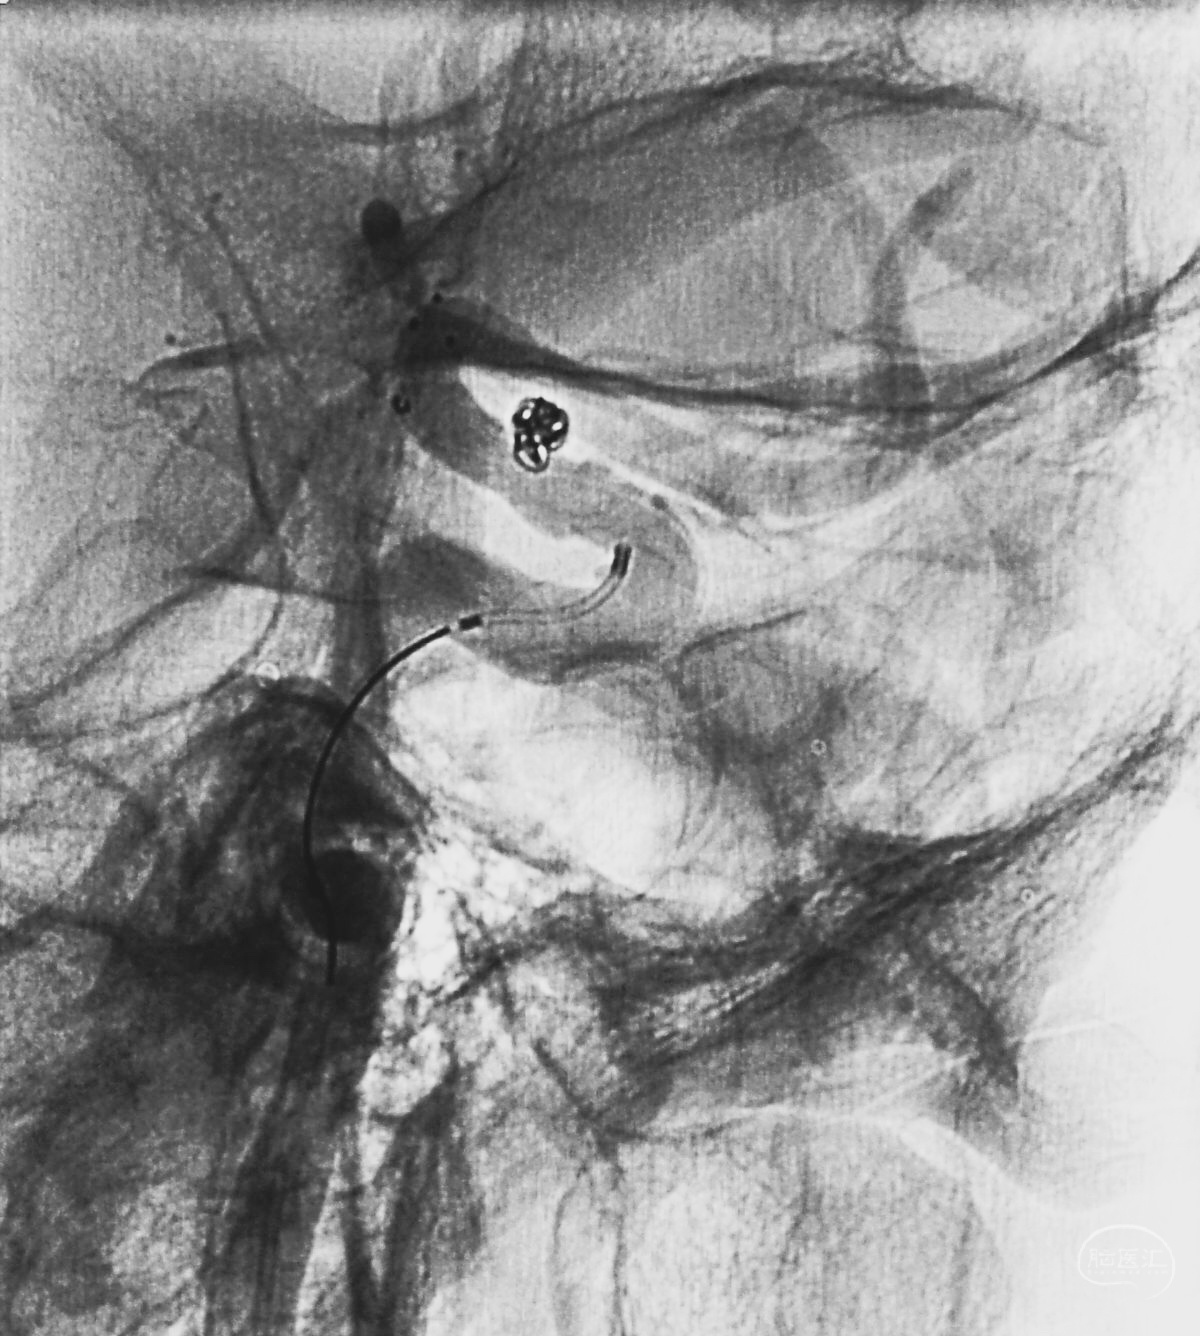

工作位造影

Traxcess 14微导丝可以进入瘤腔,但头端塑成S形的Echelon 10微导管无法跟入。

将微导管在虹吸弯处成襻,越过瘤颈,管头折返钩入瘤腔,即所谓回马枪技术。

Solitaire 4×15支架(绿线)跨瘤颈半释放,压住微导管(红线)。

经微导管向瘤腔内送入首枚弹簧圈(QC-2-4-3D)。

继续送入两枚QC-1.5-2-Helix,完全栓塞动脉瘤,部分圈突入载瘤动脉。